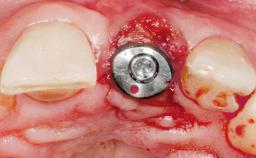

Late Placement of an Implant in a Maxillary Left Central Incisor Site

A 36-year-old female patient was referred for the replacement of the upper left central incisor (tooth 21), which had fractured. Although the tooth had been asymptomatic for many years, the crown began to loosen, at which time she presented to her dentist for an assessment. Teeth 21 and 22 had both been endodontically treated many years previously. She was a healthy individual and a non-smoker.

Type of Implants Two-Piece

Attachment Two-Piece

Bone Augmentation Horizontal|Staged

Augmentation Materials Xenogenous|Membrane

Soft Tissue Grafting Simultaneous

Abutment Type Customized